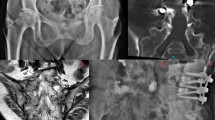

Case report describing sacral kyphoplasty in a patient with sacral hemangioma; the first account of this procedure in a sacral hemangioma.

A 74-year-old woman with known metastatic renal cell carcinoma was investigated for pain in the left sacral region. A tumoral lesion was detected, and sacroplasty was performed at S1.

The sacral pain resolved completely after the procedure, and the patient was able to walk without assistance. The pathological diagnosis for the vertebral lesion was hemangioma.

Sacral kyphoplasty is a very effective, minimally invasive surgical procedure. Patients with debilitating diseases such as primary sacral tumors or metastases can be treated by this technique with no significant complications.